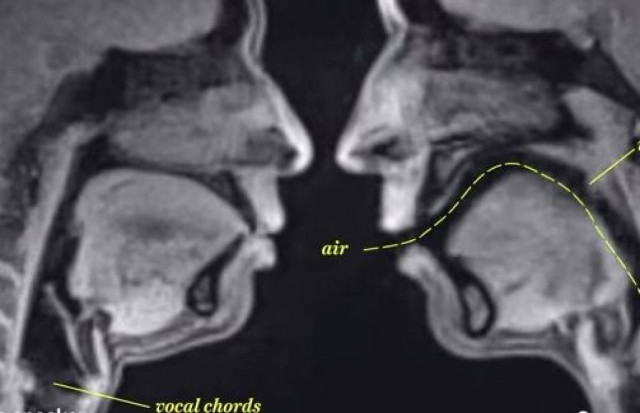

Τομογράφος παρουσιάζει το σεξ όπως δεν το έχετε ξαναδεί (vid)

SEX · 21.09.2014 - 21:20

Η σεξουαλική επαφή από άλλη οπτική γωνία...